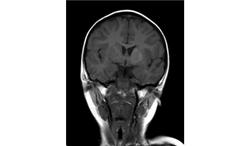

Помогите пожалуйста при постановке диагноза

Ребенок 2 года, заболели в середине декабре, гемипорез, к сожелению не могу ни как с контрасном исследованеим здесь загрузить но накапление контрасного вещества нет, спосибо за помочь!!!!!!!

Предположу гипоксически-ишемические изменения с диапедезным кровоизлиянием. Но они чаще двусторонние.